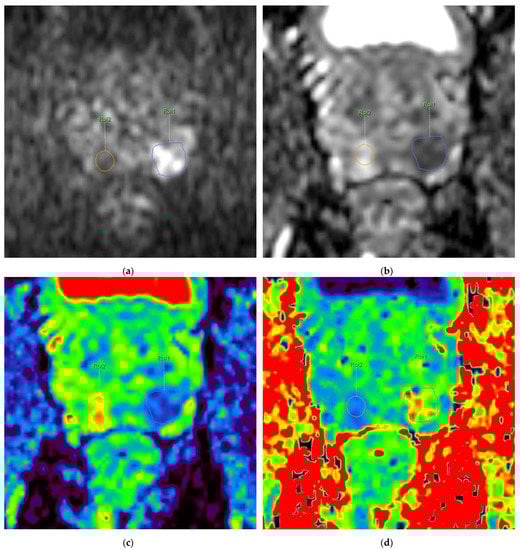

All exams were reviewed by two radiologists with 4 and 13 years of experience in prostate MRI, who identified by consensus the location and extent of PCa index lesion(s), as well as normal prostatic tissue with correlation to the histopathologic results of the prostatectomy specimens. A PI-RADS (Prostate Imaging–Reporting and Data System) score was assigned according to PI-RADS version 2.1 [24]. The radiologist with 4 years of experience obtained quantitative diffusion parameters by drawing the ROI (region of interest) on each patient’s dominant lesion(s) and benign prostatic tissue on generated maps of ADC1200; then the ROIs were automatically copied to ADC2000, D, and K maps, respectively, and the quantitative value of each parameter, as well as the goodness-of-fit, were automatically calculated (Figure 1). The ROI in the PCa foci was drawn inside the lesion excluding margins to avoid a partial volume effect.

Figure 1.

62-year-old patient with PSA level 8 ng/mL and PIRADS 5 lesion located in left PZ, that after radical prostatectomy was assessed as acinar type prostate adenocarcinoma GS 4 + 3. Images of the prostate with GS 4 + 3 lesion in left PZ (ROI 1—circled in blue) and control (ROI 2—circled in orange) in benign prostatic tissue: (a) DWI at b-value 2000 s/mm2 with high-intensity lesion in left PZ (ROI 1) and control ROI 2 in normal tissue (b) ADC map obtained with b-values 0–1200 s/mm2 with corresponding low-intensity signal in lesion in left PZ (ROI 1) of 0.68 × 10−3 mm2/s and control ROI 2 of 1.73 × 10−3 mm2/s (c) Color-coded maps of Dapp and (d) kurtosis obtained with b-values 0–2000 s/mm2 show Dapp of 0.88 × 10−3 mm2/s and kurtosis of 1.40 in ROI 1 and Dapp of 2.18 × 10−3 mm2/s and kurtosis of 0.69 in ROI 2, respectively. (e) Whole-mount prostate specimen shows GS 4 + 3 PCa in left PZ (circled with continuous line in violet); additionally, GS 3 + 4 PCa is seen in right PZ (circled with dashed line in blue). DWI signal-intensity decay plots obtained using monoexponential model (f,g) and kurtosis model (h) for different b-values (marked as dots on the graph). Graph in blue corresponds to ROI 1 in GS 4 + 3 lesion; graph in orange corresponds to control ROI 2 in normal peripheral zone (free of cancer): (f) Gaussian distribution standard monoexponential model for b-values 0, 100, 500, 800, 1200. Goodness-of-fit for ROI 1—0.96, ROI 2—0.93. (g) Gaussian distribution standard monoexponential model for b-values 0, 100, 500, 800, 1200, 2000. Goodness-of-fit for ROI 1—0.92, ROI 2—0.89. (h) Non-Gaussian kurtosis model for b-values 0, 100, 500, 800, 1200, 2000. Goodness-of-fit for ROI 1—0.99, ROI 2—0.98. Figure 1a–d,f–g are modified screenshots provided by Advanced Diffusion Analysis application, Intellispace Portal 10.